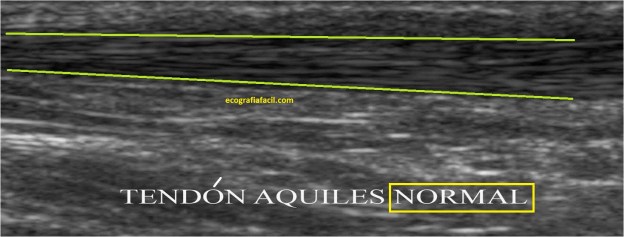

La afectación tendinosa del Aquiles cursa ecográficamente con cambios hipoecogénicos y de aumento del tamaño como puedes ver en la imagen 6 y 7, respecto de la normalidad, que vemos en la 4 y 5.

Las fibras alargadas, homogéneas, sin alteración de la ecoestructura hiperecogénica del tendón, demuestran que es un tendón sano.